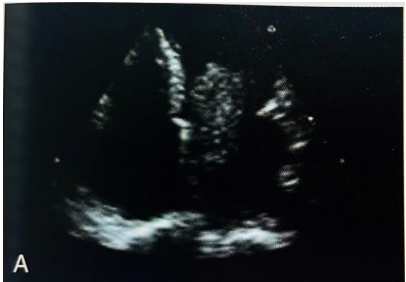

Na consulta, traz imagem de ecocardiograma transtorácico, corte quatro câmaras, com descrição de massa em átrio esquerdo com densidade homogênea, contornos irregulares, móvel, com fixação em septo interatrial, projetando-se para cavidade do ventrículo esquerdo:

BRAUNWALD. Tratado de Doenças Cardiovasculares. 9ª Ed. Figura 74-1; página 1681.